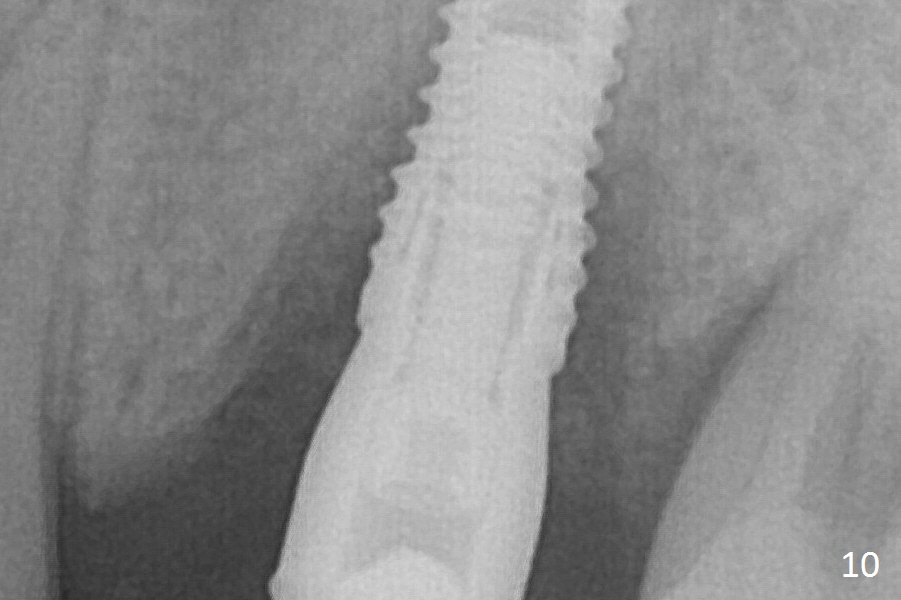

Bone density between #13 and 14 appears to increase 3 months postop (Fig.10).  There seems to be more bone growth (i.e., decreasing gap) 6 months postop (Fig.12).